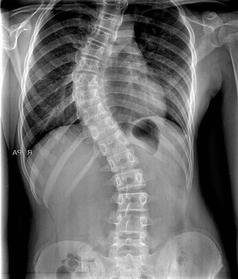

Ces rêves ou vos vertèbres ne sont pas abîmés ? Ou le radiologue n'a pas besoin de "passer un coup de fil à des experts " à chaque fois qu'il vous voit